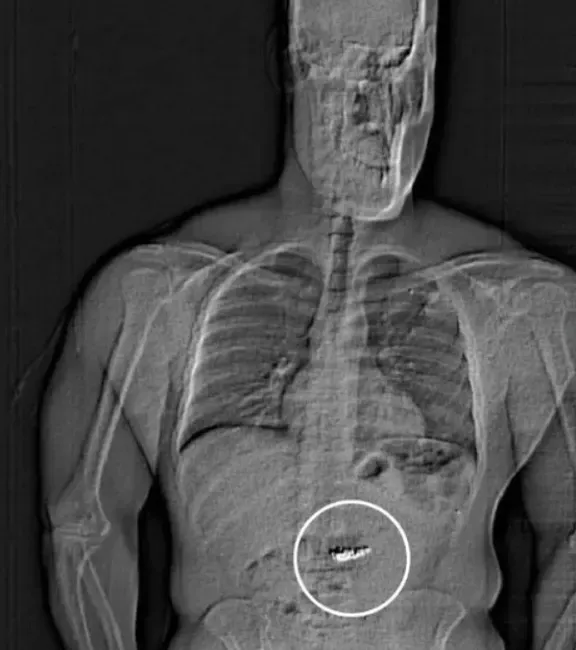

Az autójának átkutatása során nem kerültek elő az ékszerek, és a férfit kezdetben csak azzal gyanúsították, hogy "ellenállt a rendőri intézkedésnek". Később azonban röntgenes vizsgálatnak vetették alá, mely során kiderült, hogy "idegen tárgyak" haladnak át az emésztőrendszerén. Ezt követően Gilder teljes körű beismerő vallomás tett.

Az őrizetbe vételt követő napon az ékszerek is előkerültek. Mint kiderült, Gilder egy 160 ezer dollár, valamint egy 609 ezer dollár értékű fülbevalót nyelt le. Ezeket most alapos vizsgálatnak vetik alá, hogy kiderüljön, valóban a lopott ékszerekről van-e szó. Ha igen, visszaadják az ékszerboltnak.